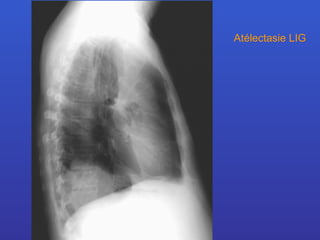

Atélectasie LIG